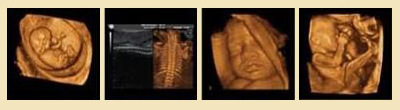

四維彩超宮內(nèi)圖